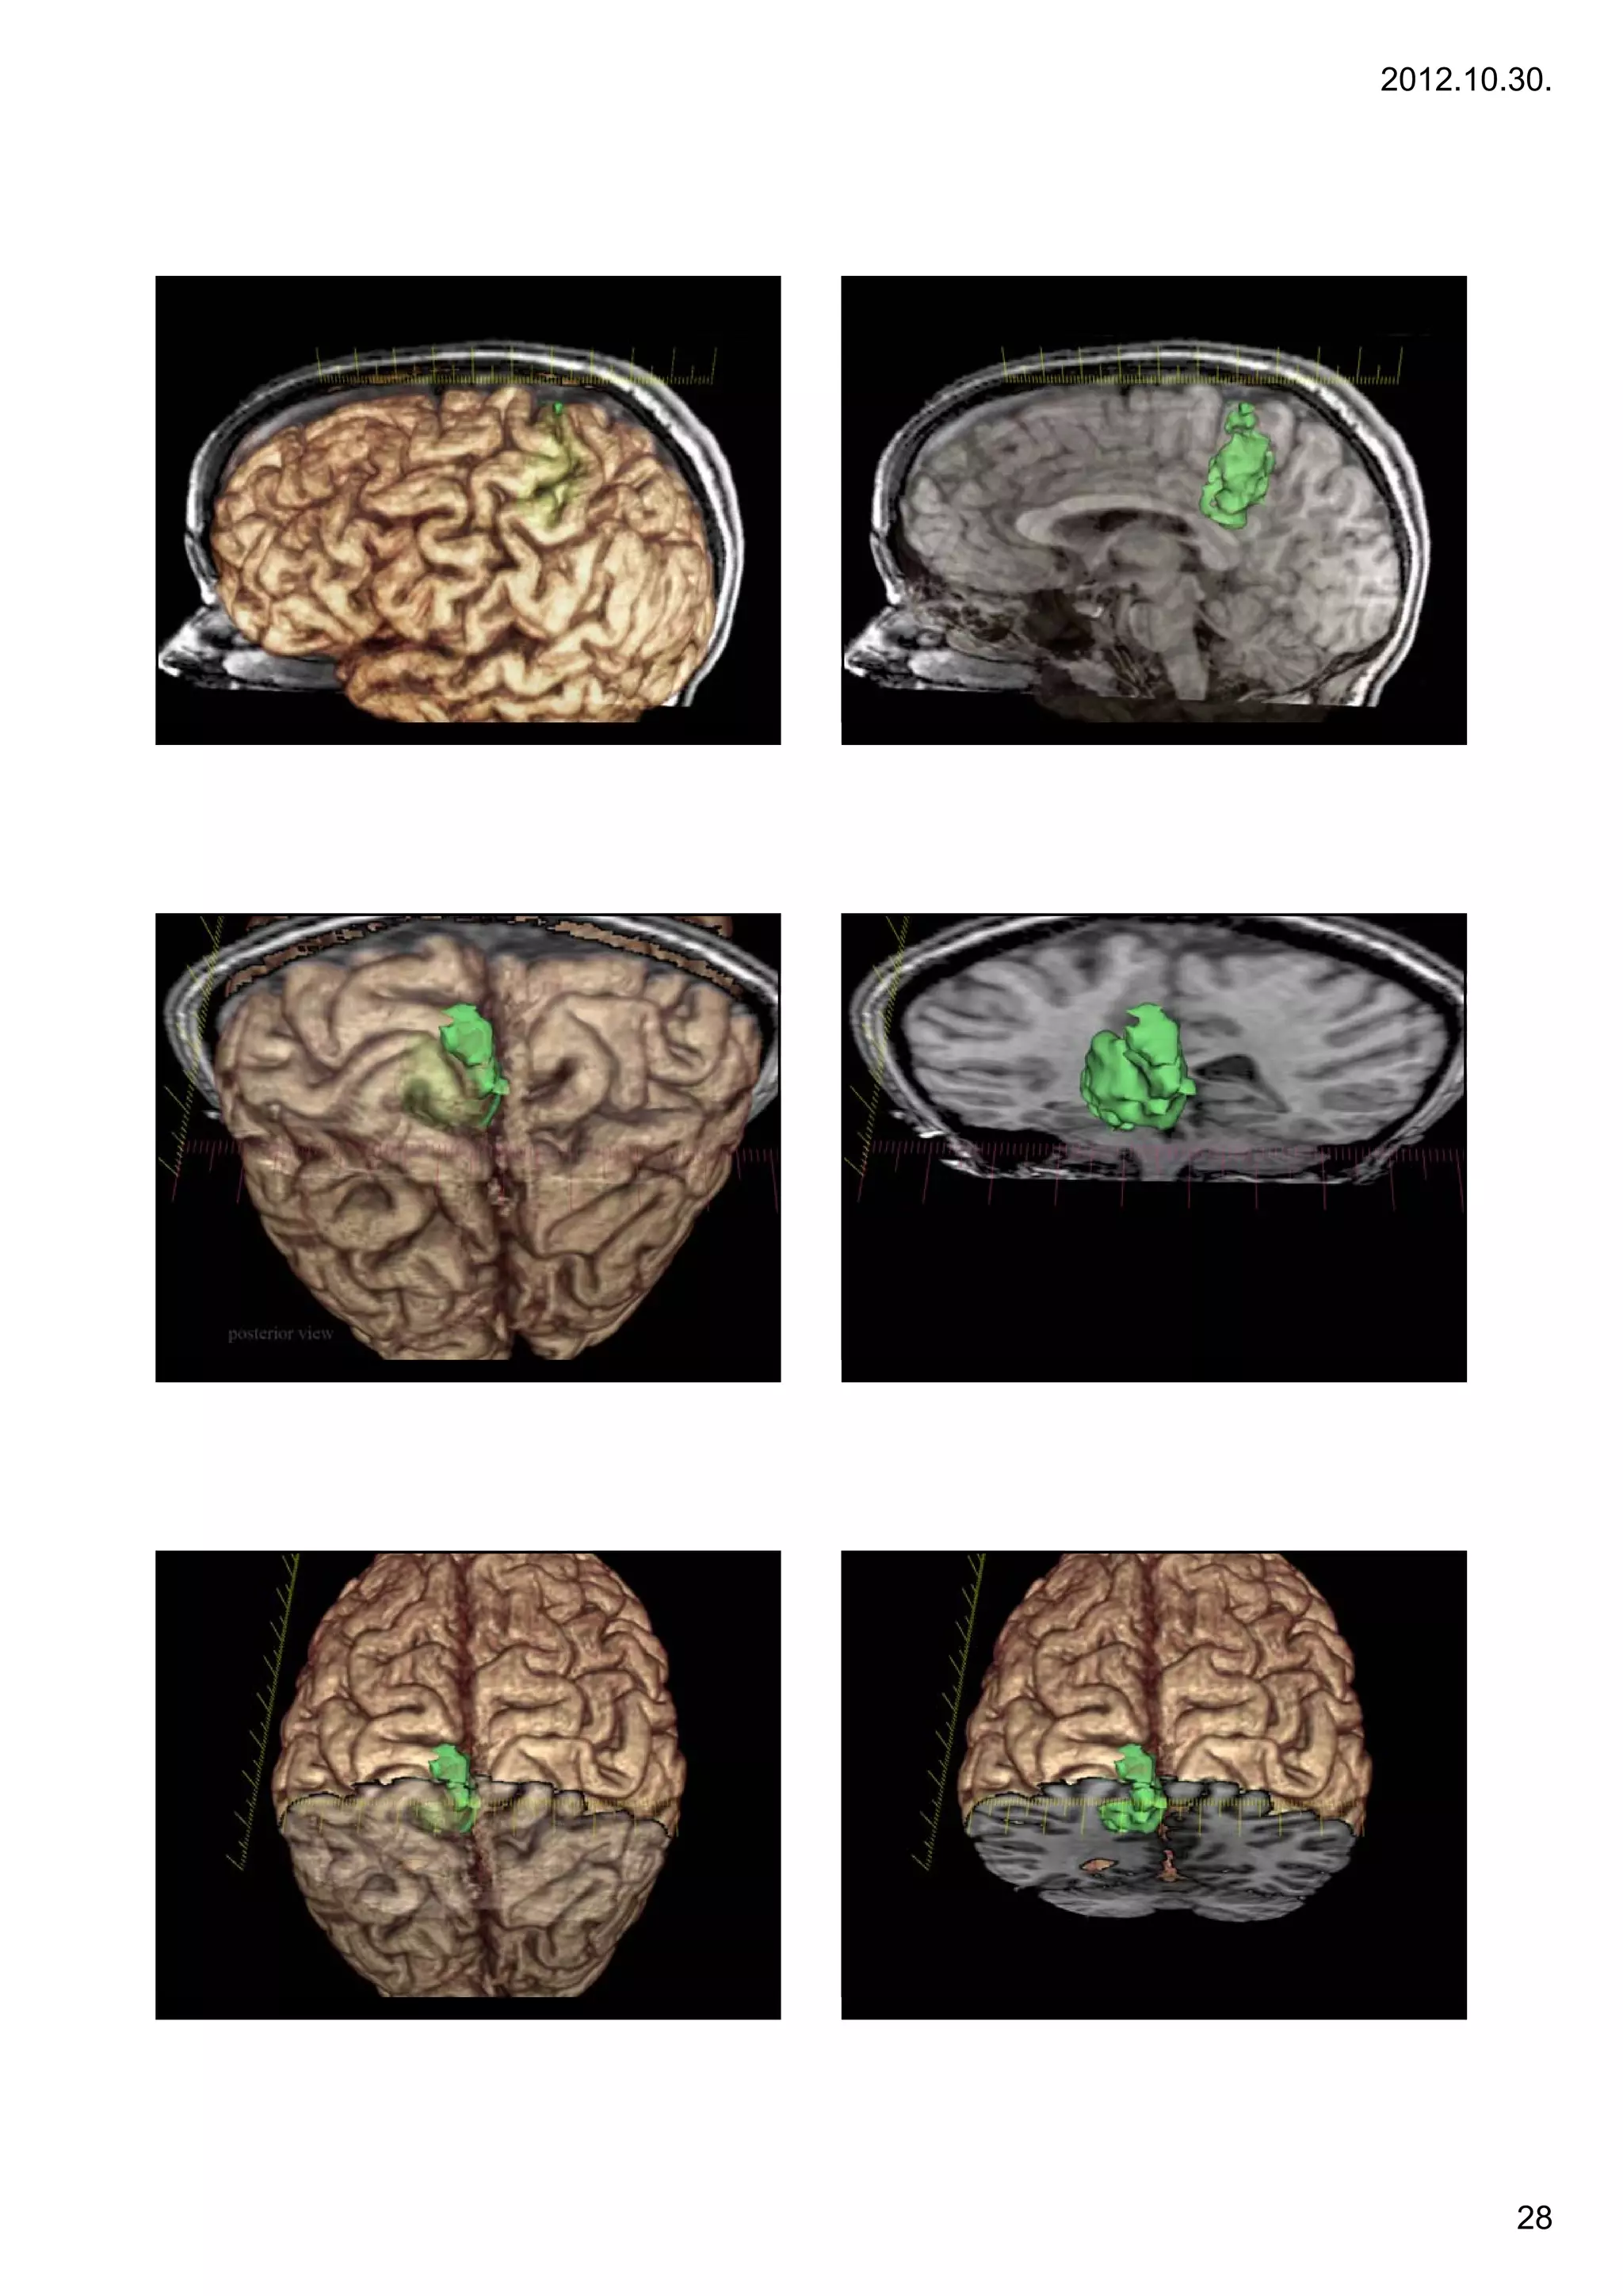

AVMs                                                       Diagnosis by angiography

•Arteriovenous malformation or AVM is an abnormal connection

between veins and arteries, usually congenital. This pathology is widely known because of its

occurrence in the central nervous system, but can appear in any location. An arteriovenous

malformation is a vascular anomaly. It is a RASopathy. The Spetzler-Martin grading system

developed at the Barrow Neurological Institute is utilized by neurosurgeons to determine

operative versus nonoperative management when approaching these lesions.

Diagnosis by angiography                                                            Diagnosis by MRI (T1 and T2-w)